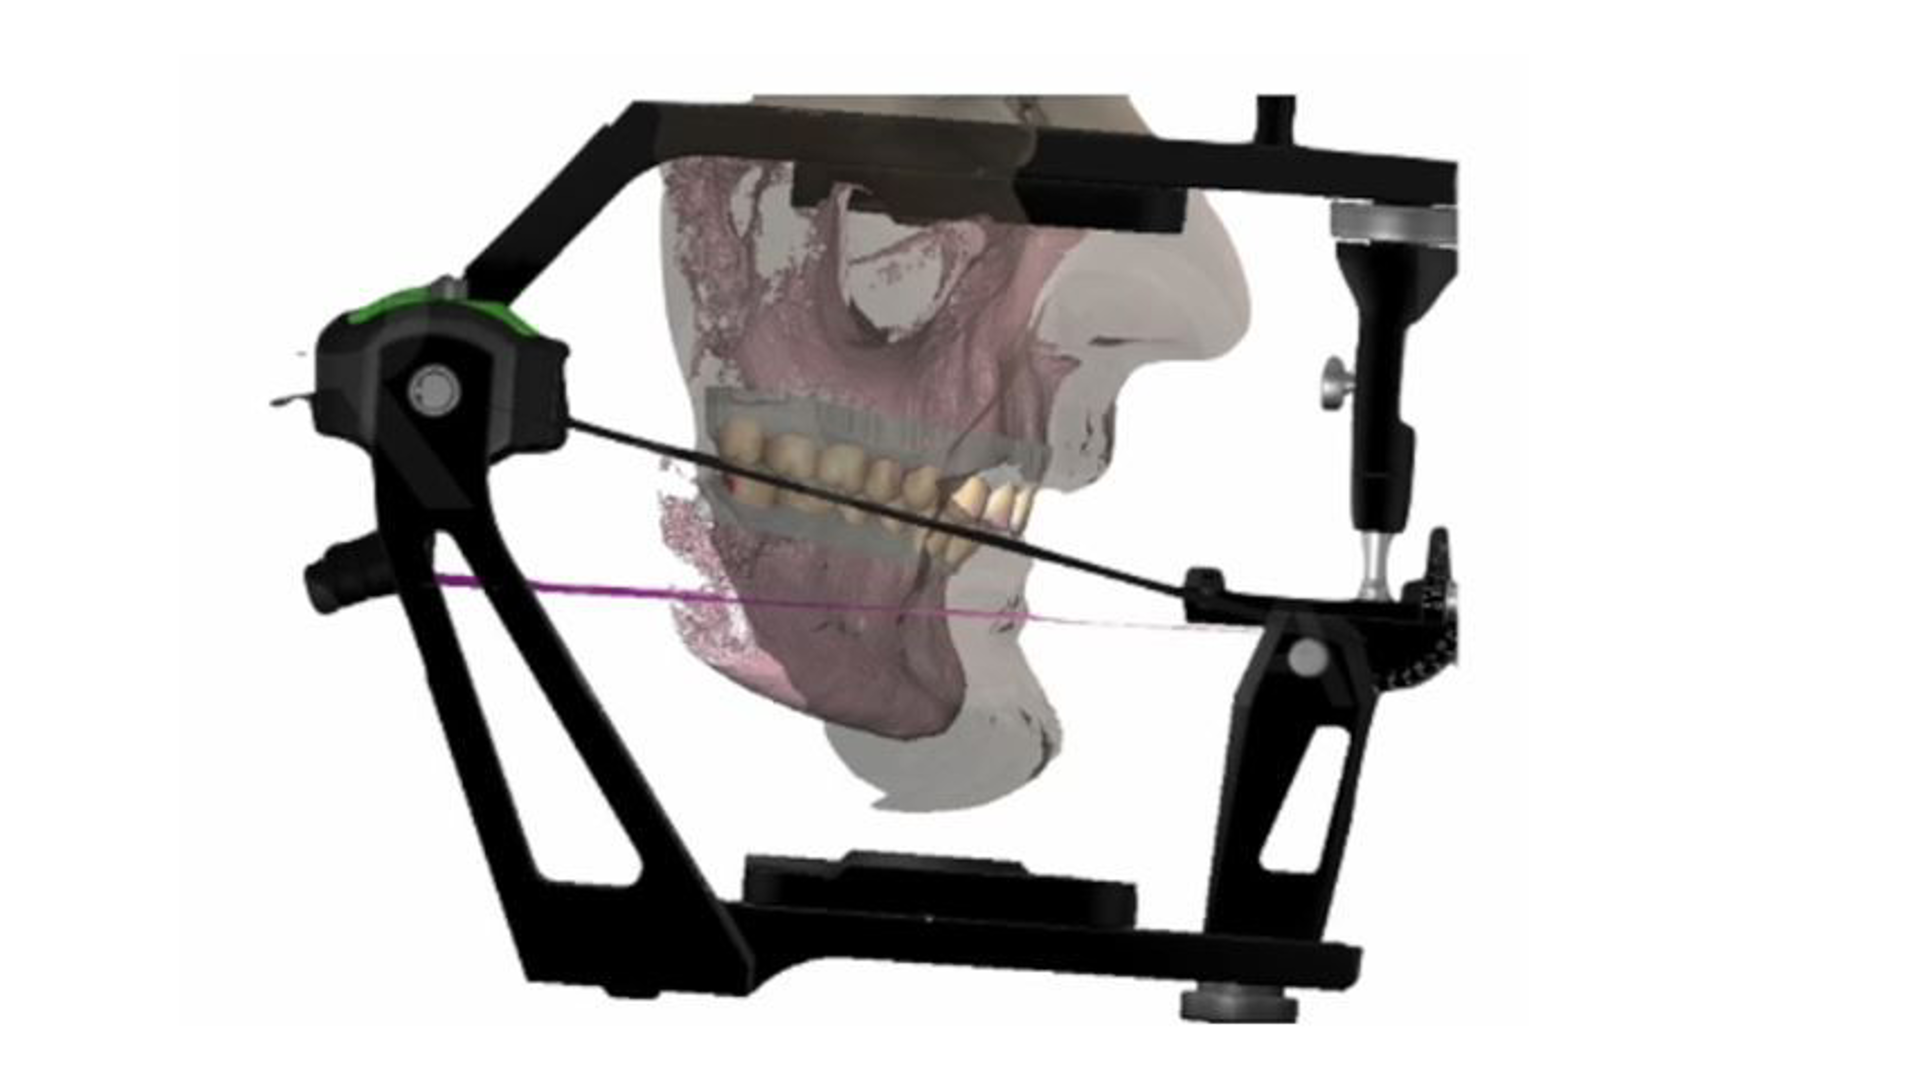

Functional analysis according to MIPP concept

The centric relation according to MIPP concept